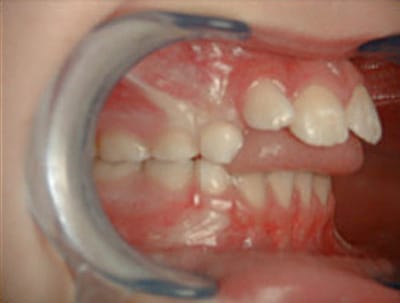

Rééducation Étude prospective sur les dyspraxies oro-faciales et dysfonctionnement de l'appareil manducateur entre un groupe de nageurs et un groupe témoins